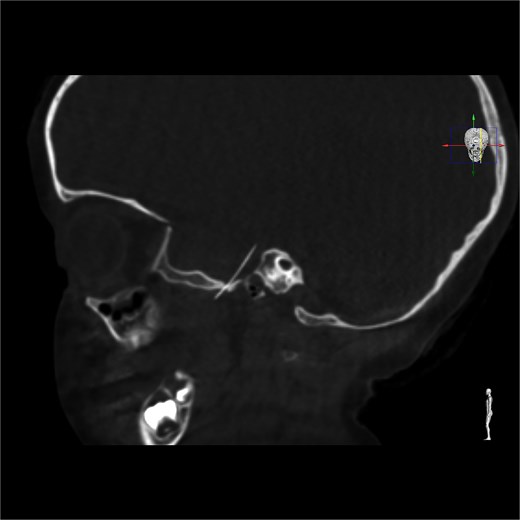

Neuronavigation-assisted surgery was then performed. The patient underwent a right pterional craniotomy (Fig. 3). Extradural dissection was conducted until Meckel’s cavum. The dura was carefully opened directly over the needle, which was completely removed through the craniotomy to avoid injury to the temporal lobe. The patient was admitted for a week of post-operative monitoring and received standard prophylactic intravenous medication. After 8 days, she had recovered well and was discharged. The patient remained asymptomatic throughout the entire process.

Pterional approach to reach the needle guided by neuronavigation.